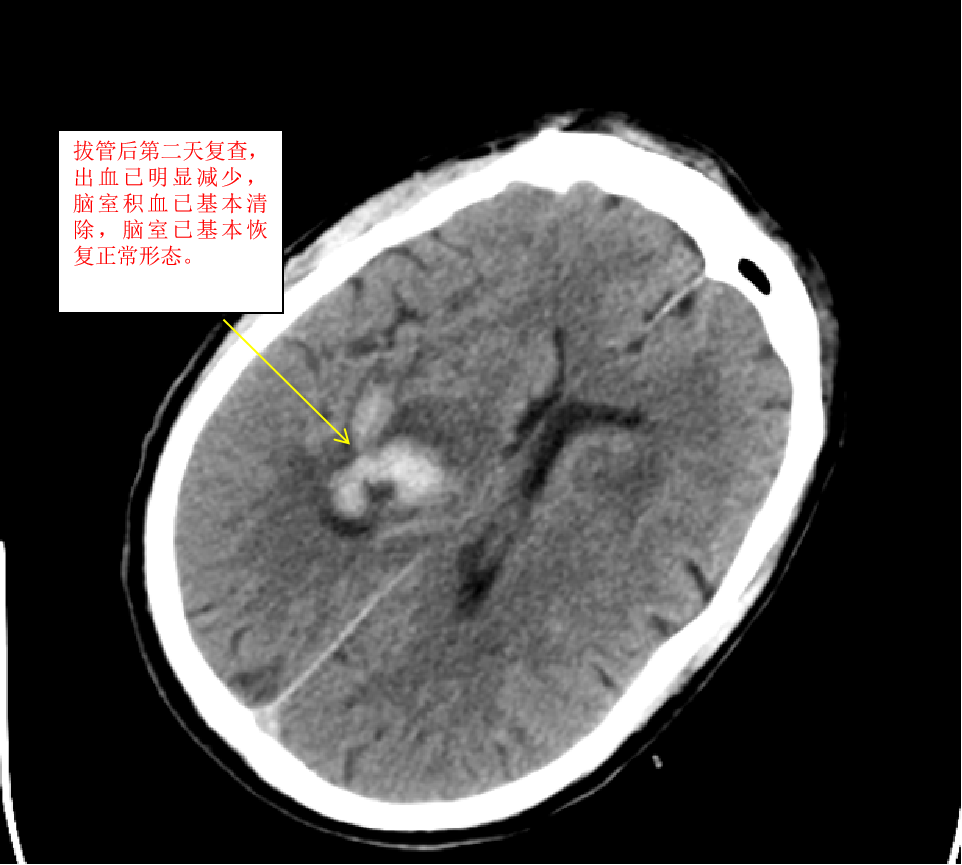

我们收到此病人后,立即给予术前准备,并在局麻下行双侧脑室外引流术,由于病人脑室有大量出血,穿刺置管有很大的技巧,因为大量的脑室出血,致脑室铸型,打乱了正常的解剖结构,穿刺失败的可能性很大。经术后复查颅脑CT,发现右侧管道引流较通畅,决定拔除左侧引流管,并通过右侧引流管给予尿激酶注入反复溶解血块并引流出血性液体,共应用尿激酶10次,每日一次,为了预防感染,并在每次冲洗时给予严格换药。于第10天经复查颅脑CT发现脑室出血已基本清除,决定给予拔除脑室引流管。为了放出残留血性脑脊液,尽量廓清病人脑脊液,于拔管后第二天开始给予腰穿,共进行腰穿10次,每日一次,腰穿时尽量多放出脑脊液,才能取得更好的效果。于近日复查颅脑CT发现丘脑出血已完全吸收,脑室积血已完全清除,未出现脑积水,未出现颅内感染。经过这段时间的治疗后病人的意识状况已明显好转,由深昏迷转为神志恍惚,肢体的偏瘫也逐渐好转,目前仍给予肢体康复训练治疗,几天后就能治愈出院。